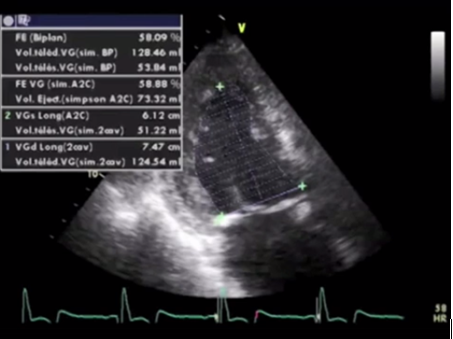

Методы оценки систолической функции левого желудочка:

- измерение ФВ ЛЖ в 2D режиме по Simpson;

Методом выбора в оценке систолической функции миокарда является исследование фракций выброса левого желудочка при помощи эхокардиографии. Наилучшими являются измерения при помощи трехмерной эхокардиографии, а используемые иногда измерения в одномерном М-режиме по методу Тейхольца проводить нельзя, в связи с большим количеством неточностей и погрешностей. И при отсутствии трехмерной эхокардиографии исследование выполняется в двухмерном режиме по методу Симпсона.

Измерение ФВ ЛЖ в 2D режиме по Simpson

- При применении ЭхоКГ предпочтительно использовать показатели ФВ ЛЖ, полученные при ЗD-исследовании, а при отсутствии технической возможности — ФВ ЛЖ в 2D-режиме по методу Симпсона. Показатели ФВ ЛЖ, полученные при измерении в одномерном режиме (по Тейхольцу) использовать не рекомендуется.

- Нижней границей нормы ФВ ЛЖ для пациентов, получающих противоопухолевую терапию, является значение в 50%. А диагностический критерий дисфункции – снижение ФВ ЛЖ на 10% и более от исходной величины (снижение должно быть меньше нижней границы нормы или 50%).